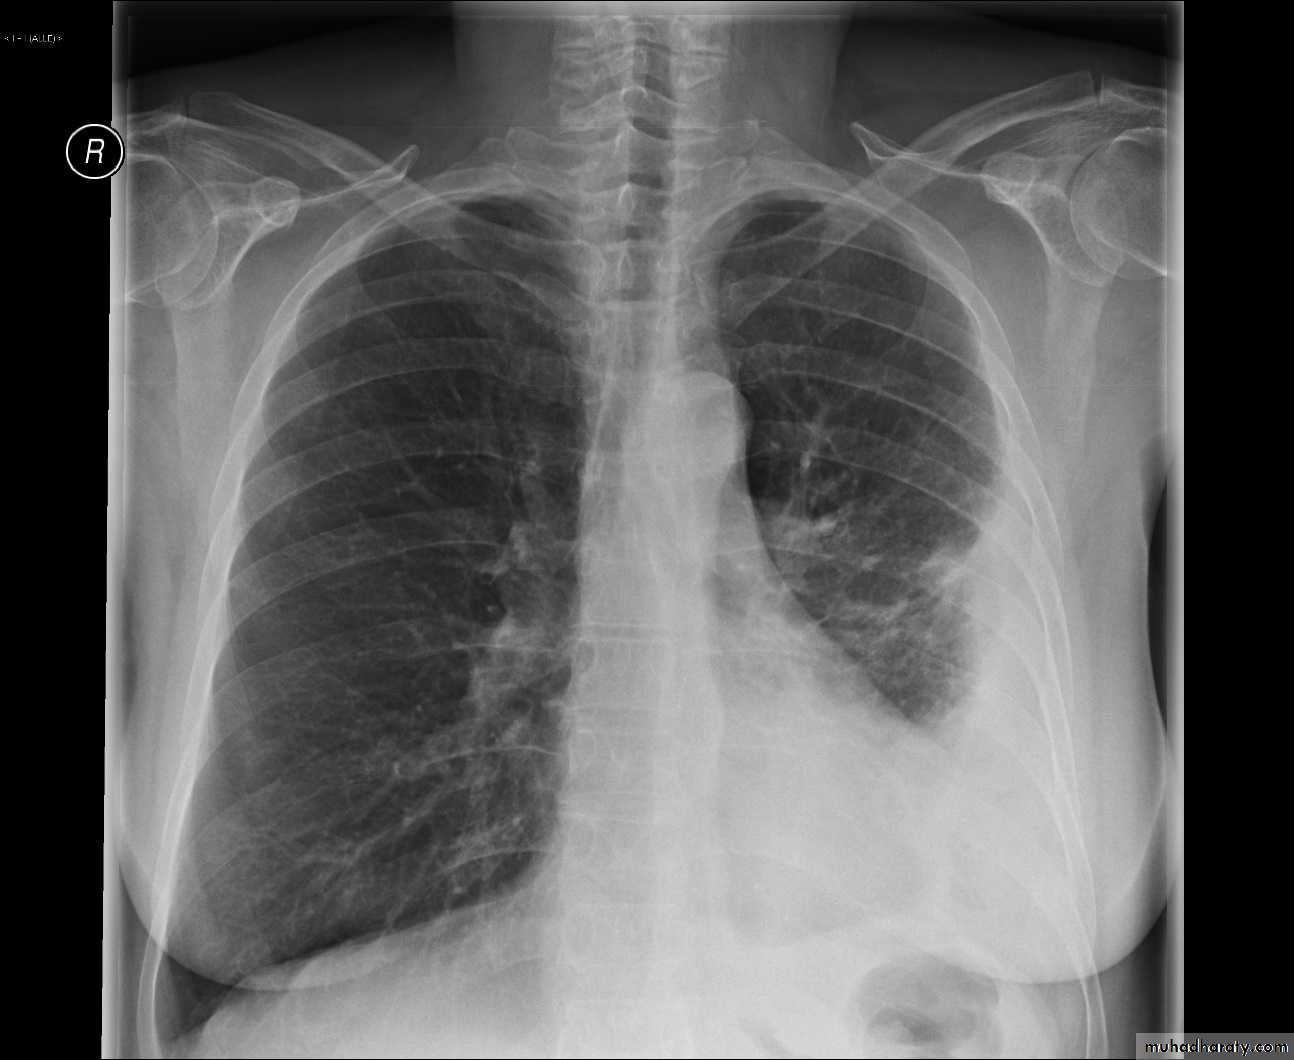

X-ray hemothorax

X-ray pneumohemothorax